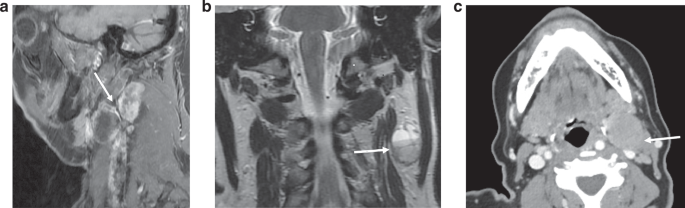

The broad patterns of disagreement after first reading as shown in Table 1 were shared with the 4 radiologists. This highlighted one major area of disagreement: where one radiologist scored iENE 0 and the other scored iENE=1. The radiologists met to review and address these data, share their experiences, review the iENE assessment criteria, and collectively review several non-study cases to promote inter-rater concordance in iENE assessment—a method that has been used by others [14]. The following principles were agreed upon, illustrated in the examples in Fig. 2a–c:

a Grade 1 iENE: Sagittal T1FS+c MRI– showing two adjacent metastatic Level II + III nodes with irregular nodal margins and perinodal fat stranding, but with a clear fat plane separating the 2 nodes. These nodes had appeared to be coalescent on axial images but review of coronal + sagittal imaging planes resulted in Grade 1 iENE. b Grade 0 iENE: Coronal T2 MRI showing cortical lobulation within a cystic metastatic Level II node (arrow), lobulation of a single metastatic node should be should be distinguished from coalescence of adjacent nodes to avoid overcalling Grade 2 iENE. This node has a well-defined margin and there is no perinodal fat stranding, therefore Grade 0 iENE. c Grade 0 iENE: Axial CECT demonstrating loss of the fat plane between a metastatic Level II node and sternocleidomastoid muscle (arrow). However, there is no extranodal enhancement to indicate muscle invasion of the muscle (compare with Fig. 2d), therefore Grade 0 iENE.